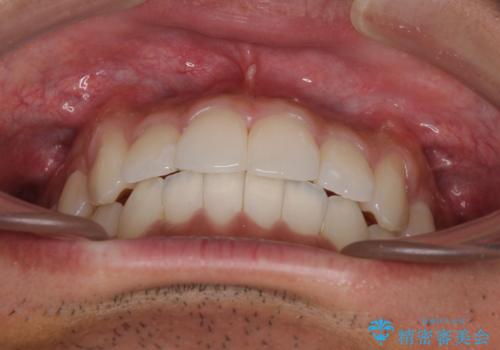

前歯のデコボコを治したい インビザライン矯正治療

- 前歯のデコボコを治したいとのことで来院された患者様です。

上下顎ともに歯列全体の後方移動とIPR(歯と歯の間を削る)によってデコボコが解消するように設計し、インビザラインにより治療を行うこととしました。

毎日22時間以上しっかりとマウスピースを装着していただいたので、スムーズに治療が進みました。歯と歯の間を削ることでうまくスペースコントロールでき、1年強で終えることができました。